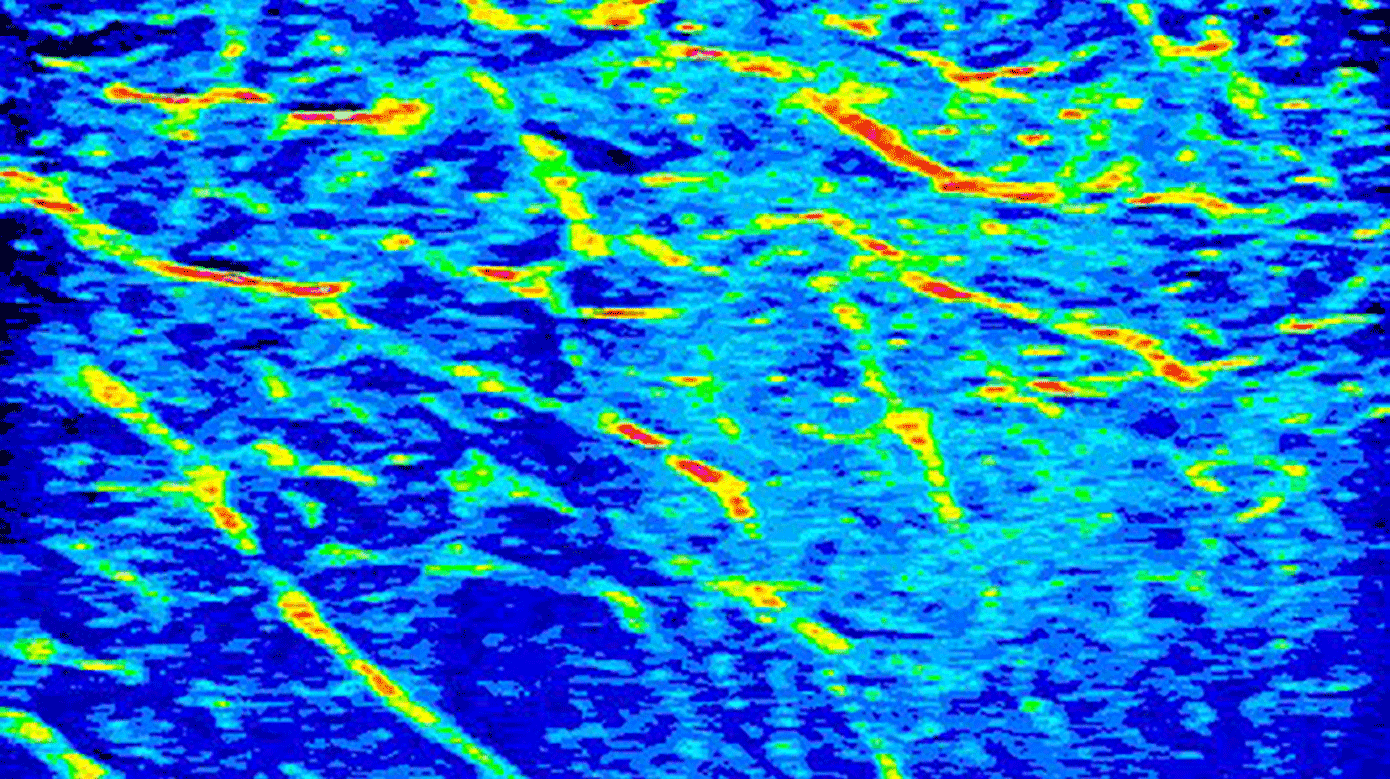

Alle UL-billeder blev gemt på en harddisk og efterfølgende behandlet i R med pakken »EBImage«. Her blev billederne dikotomiseret ud fra værdier fra tidligere studier med en gråskala 48-128. Dette skulle svare til væskeholdigt interstitiel væske. Antallet af pixels i dette interval blev summeret og divideret med total antal pixels. Dette udgjorde procentdelen af væskeholdigt kød.

Efter UL-skanning af stegene havde steg nr. 1 64,26% væskeholdigt kød, steg nr. 2 havde 58,15% væskeholdigt kød, og steg nr. 3 havde 60,33% væskeholdigt kød. Ved steg nr. 3 var begge skanninger i yderste inddeling væsentligt forskellige fra de andre, og ved inspektion af skanningsbillederne var der artefakter på begge billeder. Derfor blev disse billeder fjernet fra analysen, og andelen af væskeholdigt kød blev beregnet. Eksempel på skanningsbillede i 16-bit farveskala ses i Figur 1.